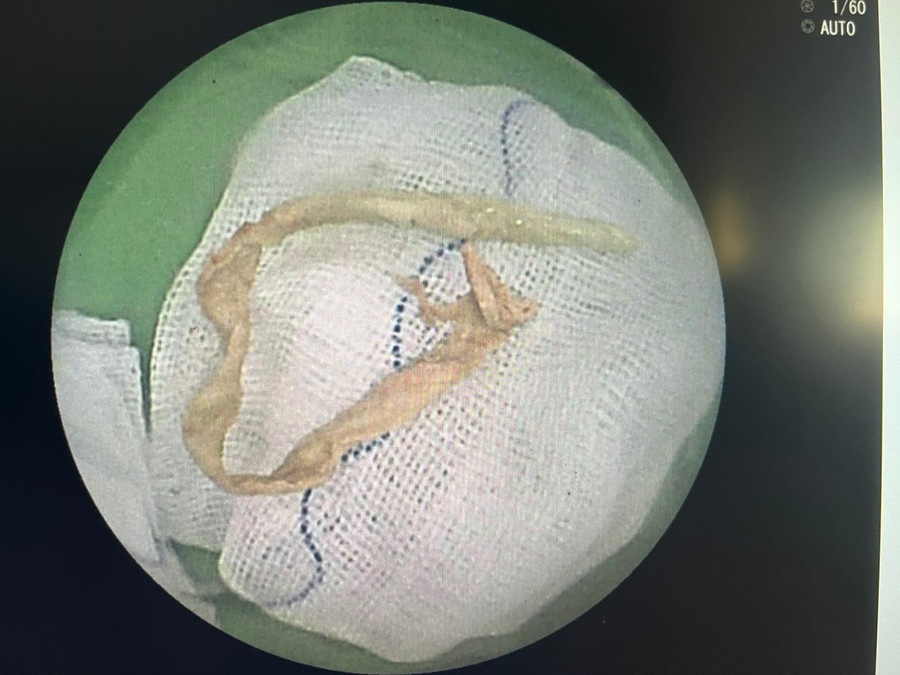

| Dị vật là đoạn khăn giấy (được se nhỏ) dài 15cm rơi trong lòng phế quản bệnh nhân. |

Sau gần 1 giờ nỗ lực, ê-kíp nội soi đã lấy thành công dị vật đoạn khăn giấy (được se lại) kích thước khoảng 0.5 x 15cm. Hiện sức khỏe bệnh nhân ổn định, phổi thông khí tốt, không còn triệu chứng kích thích hô hấp đang được chăm sóc và theo dõi tại bệnh viện